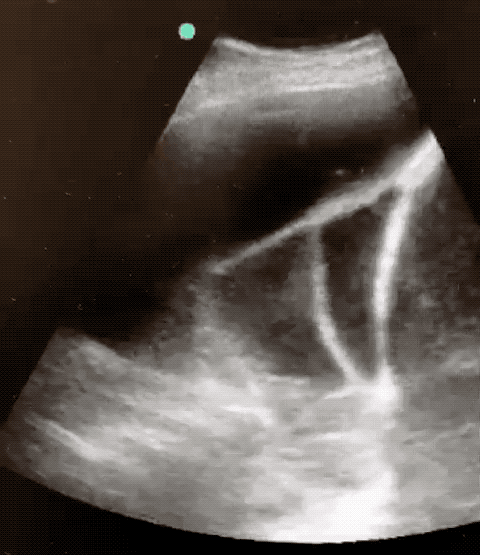

• loculations on imaging